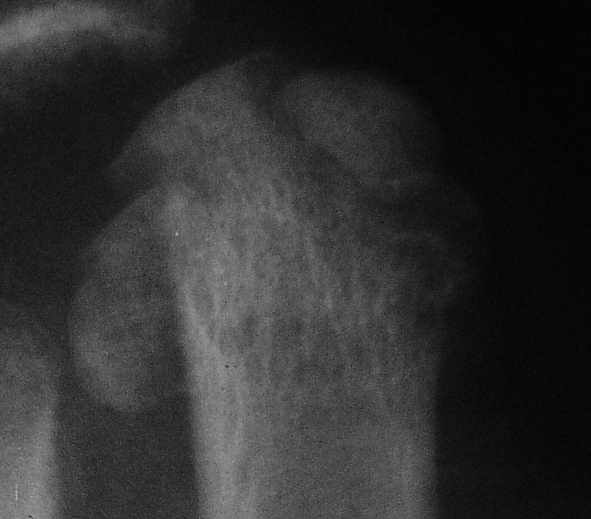

3 кстати, Вы перелом пкрвой плюсневой видите? В каком месте и на каком снимке?

Вот головка более прицельно.